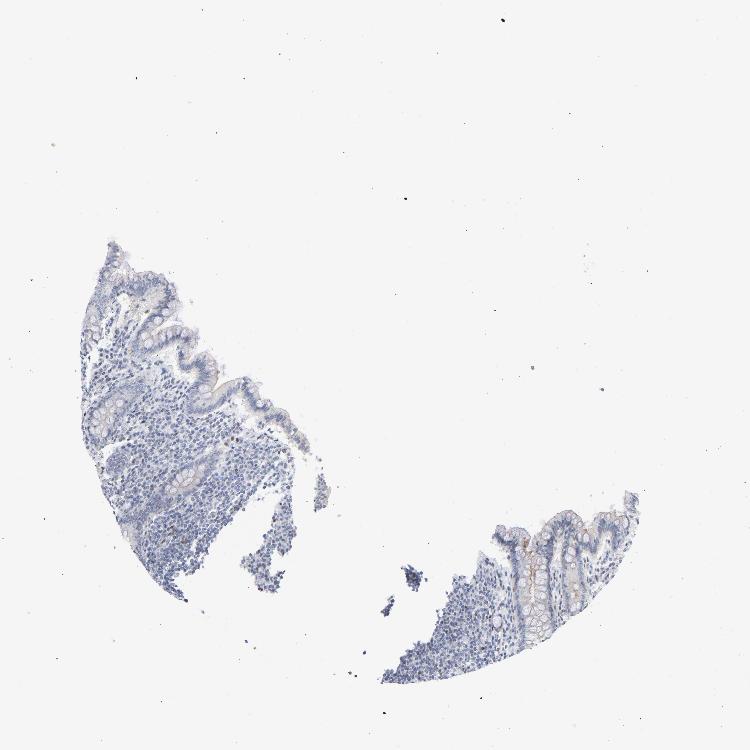

APPENDIX - Expression summary

APPENDIX - Antibody stainingi

Antibody staining in the annotated cell types in the current human tissue is reported as not detected, low, medium, or high, based on conventional immunohistochemistry profiling in selected tissues. This score is based on the combination of the staining intensity and fraction of stained cells.

Each image is clickable and will lead to virtual microscopy that enables deeper exploration of all samples and also displays staining intensity scores, fraction scores and subcellular localization as well as patient and tissue information for each sample.

Antibody HPA052625Antibody CAB004300Antibody CAB004674

Endocrine cells Not detected--

Enterocytes Low--

Enterocytes - Microvilli Not detected--

Germinal center cells Medium--

Glandular cells -Not detectedNot detected

Goblet cells Not detected--

Lymphoid tissue --Low

Non-germinal center cells Medium--